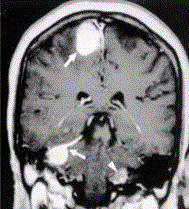

问题 患者男,20岁,头痛、步态不稳。MRI显示如下图。 可能的诊断是

选项 A.神经纤维瘤病Ⅱ型 B.神经纤维瘤病Ⅰ型 C.多发脑膜瘤 D.多发神经鞘瘤 E.多发转移瘤

答案 A